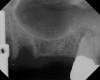

The implant is then delivered and should be well stabilized in the bone. If there is any mobility of the implant, it can either be placed a little deeper (if there is enough native bone) or the implant can be removed and the procedure aborted, in which case it would be a two-stage procedure. This should rarely occur with the tapered designed implant, even with only 2 mm of native bone. Using a bone-level platform-shifting implant (or a tissue-level designed implant) is critical, as the hard and soft tissue will establish a biologic width. If an external hex type of implant is used and the shoulder is placed at the bone level, an expected bone loss of 1.5 mm to 2 mm will occur.24 Figure 10 shows proper bone-level implant depth placement with a platform-shifting design. In this case, a 3-mm healing abutment was placed at the time of surgery to avoid a secondary uncovering surgery, but an implant-level healing abutment could have been placed instead. As can be seen, there was only about 2 mm to 3 mm of native bone height. The membrane was raised about 8 mm to 9 mm. Comparing the radiograph on the day of surgery (Figure 10) to the 6-month postoperative radiograph (Figure 11) shows no loss of native bone, as well as the positive change in appearance of the grafted bone. The 3.5-month CBCT scan (Figure 12) shows good healing of the bone with no coronal bone loss. With minimal native bone present, as in this case, the use of a non-platform-shifting or non-tissue-level implant design could be problematic. After 1.5 mm to 2 mm of crestal bone loss, an external hex designed implant could develop instability with possible implant failure. If a non-tapered implant is used and bone loss occurs during healing, migration of the implant into the sinus could potentially occur. The surgeon can use either a healing abutment or implant-level closure screw over the implant shoulder. With patients who tend to use their tongues to explore or play with the area, or if the area is under a removable partial denture, a closure screw is recommended.

A 74-year-old man presented with only about 2 mm to 3 mm of native bone below the sinus in the No. 14 position (Figure 13). The composite graft used was an approximately 50:50 mixture of DFDBA (Bio-Oss®, Geistlich Biomaterials, www.bio-oss.com) with the addition of about 40% calcium sulfate by volume (Figure 14). The implant placed (Figure 15) was a 10-mm long, rough-surfaced, platform-shifting implant (tapered 4.2 mm to 2.8 mm), and the sinus was raised about 8 mm. The postoperative radiograph taken at 4 months (Figure 16) showed some shrinkage of the graft, but no demarcation of the old sinus floor in the area.